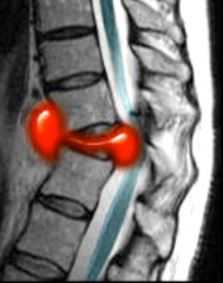

Сирингомиелитические кисты как отдалённое последствие спинальной травмы встречаются у 3-4% пациентов с неврологическими нарушениями. В целом, они относятся к отдалённым последствиям трамы, хотя известны случаи раннего формирования сирингомиелитических кист. Чаще кисты выявляются при МРТ грудном отделе спинного мозга. Замечена связь сирингомиелитических кист с деформацией позвоночного канала и посттравматическим его стенозом. В отличие от истинной сирингомиелии они развиваются на фоне атрофии и обычно не сопровождаются вздутием спинного мозга. Кисты наблюдаются с одинаковой частотой как выше, так и ниже уровня травмы. Протяжённость кисты может быть любой. Содержимое кисты обычно ликворное, но бывает и с примесью белка, что повышает сигнал от её содержимого на Т1-зависимых МРТ. На Т2-зависимых МРТ в кисте могут быть зоны потери сигнала, что отражает повышенное давление внутри неё. Отмечено, что дренаж кист в этих случаях наиболее эффективен. Изредка при МРТ в кистах встречаются перегородки.

МРТ шейного отдела позвоночника. Кистозно-атрофические изменения. Т2-взвешенная сагиттальная МРТ.